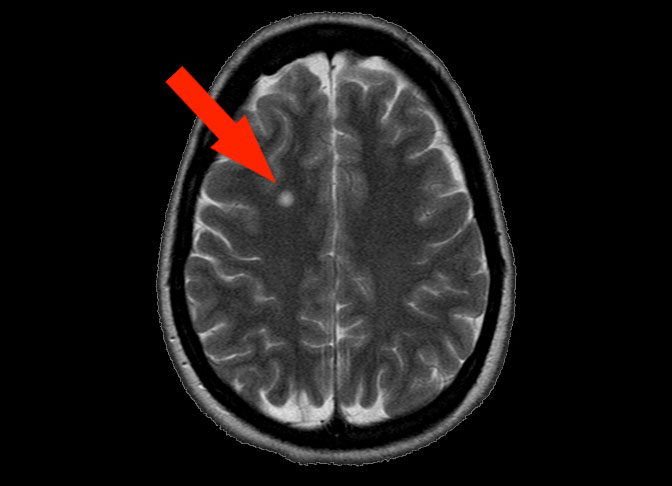

MRI Image of a lesion (red arrow) in my brain.

MS is often diagnosed with magnetic resonance imaging (MRI) scans of the patient’s CNS.

When a nerve is damaged, scar tissue forms over the damaged area. These scars, also referred to as plaques or lesions, will appear as bright areas in an MRI scan.

A substance called Contrast is often injected into a patient, before an MRI scan, to make lesions easier to see.

The presence of lesions combined with symptoms characteristic of MS, usually indicate that the patient has MS. Other tests are often performed to help eliminate the possibility of the patient’s symptoms being caused by other disorders or diseases.